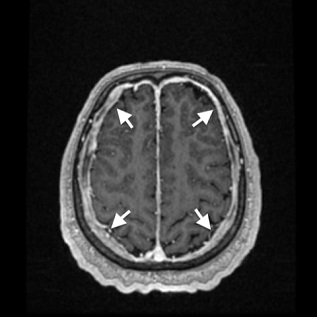

Case description: A 59-year-old Caucasian man presented with transitional episodes of tinnitus and an unspecific headache. Imaging studies (magnetic resonance imaging – MRI) demonstrated a thickened dura mater. Lymphoma was suspected due to an abnormal flow cytometric analysis of a cerebrospinal fluid (CSF) sample. Hematological diagnostics including bone marrow biopsy, whole body computed tomography (CT) and digestion tract examination were performed leading to the exclusion of hematological malignancy. The patient underwent surgery, and a specimen from the lesion was obtained. On this basis, intracranial idiopathic hypertrophic pachymeningitis was diagnosed. First line treatment strategy was introduced with corticosteroids with a gradual dose reduction. After the 48-month follow-up, we observed an alleviation of symptoms with a gradual significant decrease in the thickening of dura matter with almost complete resolution.